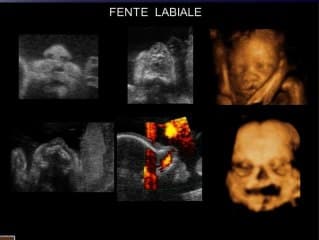

L’apport du 3D dans l’étude d’une fente labio-palatine est expliquée en détail, avec de nombreux exemples. Mais le diagnostic positif ou négatif de certitude d’une fente palatine reste incertain. L’apport de rendu surfacique du palais est aléatoire et très fœtus dépendant.